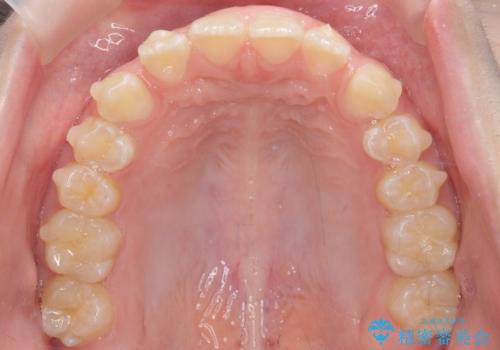

- 前歯の隙間を主訴に来院。

顎の大きさに比べて歯が小さく、隙間が目立っていました。

マウスピース矯正で隙間を閉じる処置を行いました。

隙間を閉じる際、奥歯が倒れたため、途中ワイヤー矯正を併用しています。

上の前歯の隙間を閉じながら前歯を後方に下げているため、口元もひっこみ、口が閉じやすくなりました。